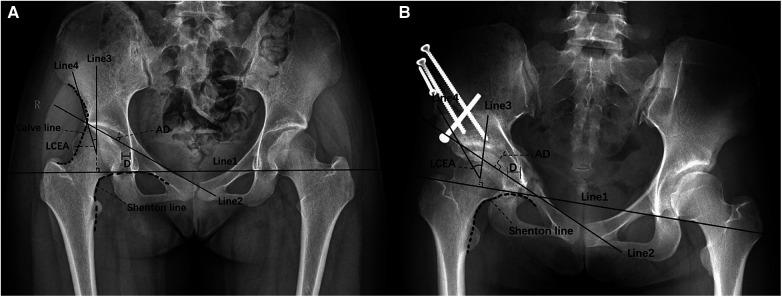

The analysis identified critical factors affecting functional recovery post-PAO, namely, the preoperative distance from the innermost surface of the femoral head to the ilioischial line, the surgical approach, preoperative acetabular depth, and the continuity of the preoperative Calve line. A nomogram was developed using these significant predictors. The model's validity was demonstrated by the receiver operating characteristic curve, with an area under the curve of 0.864. Additionally, the calibration curve confirmed the nomogram's accuracy, showing a strong correlation between observed and predicted probabilities, indicating high predictive accuracy.

分析确定了影响PAO术后功能恢复的关键因素,即术前股骨头最内表面到髂坐线的距离、手术入路、术前髋臼深度以及术前卡尔维线的连续性。利用这些重要预测指标绘制了列线图。通过受试者工作特征曲线验证了模型的有效性,曲线下面积为0.864。此外,校准曲线证实了列线图的准确性,显示观察到的概率与预测概率之间有很强的相关性,表明预测准确性高。